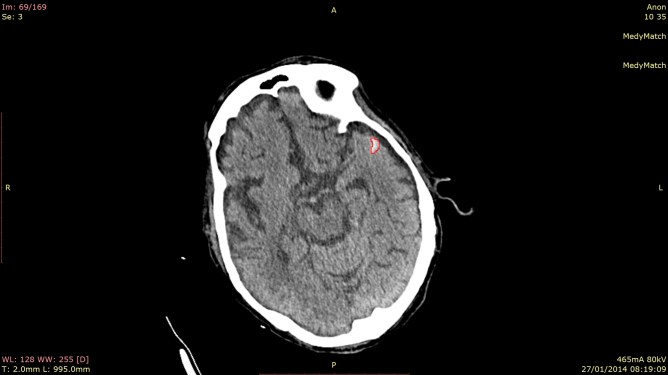

medymatch